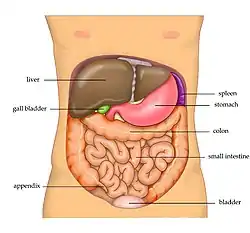

The human liver is located in the upper right abdomen | |

Location of human liver (in red) shown on a male body | |

The liver is a major metabolic organ only found in vertebrate animals, which performs many essential biological functions such as detoxification of the organism, and the synthesis of proteins and biochemicals necessary for digestion and growth.[2][3][4] In humans, it is located in the right upper quadrant of the abdomen, below the diaphragm and mostly shielded by the lower right rib cage. Its other metabolic roles include carbohydrate metabolism, the production of hormones, conversion and storage of nutrients such as glucose and glycogen, and the decomposition of red blood cells.[4]

The liver is a dark reddish brown, wedge-shaped organ with two lobes of unequal size and shape. A human liver normally weighs approximately 1.5 kilograms (3.3 pounds)[9] and has a width of about 15 centimetres (6 inches).[10] There is considerable size variation between individuals, with the standard reference range for men being 970–1,860 grams (2.14–4.10 lb)[11] and for women 600–1,770 g (1.32–3.90 lb).[12] It is both the heaviest internal organ and the largest gland in the human body. It is located in the right upper quadrant of the abdominal cavity, resting just below the diaphragm, to the right of the stomach, and overlying the gallbladder.[5]